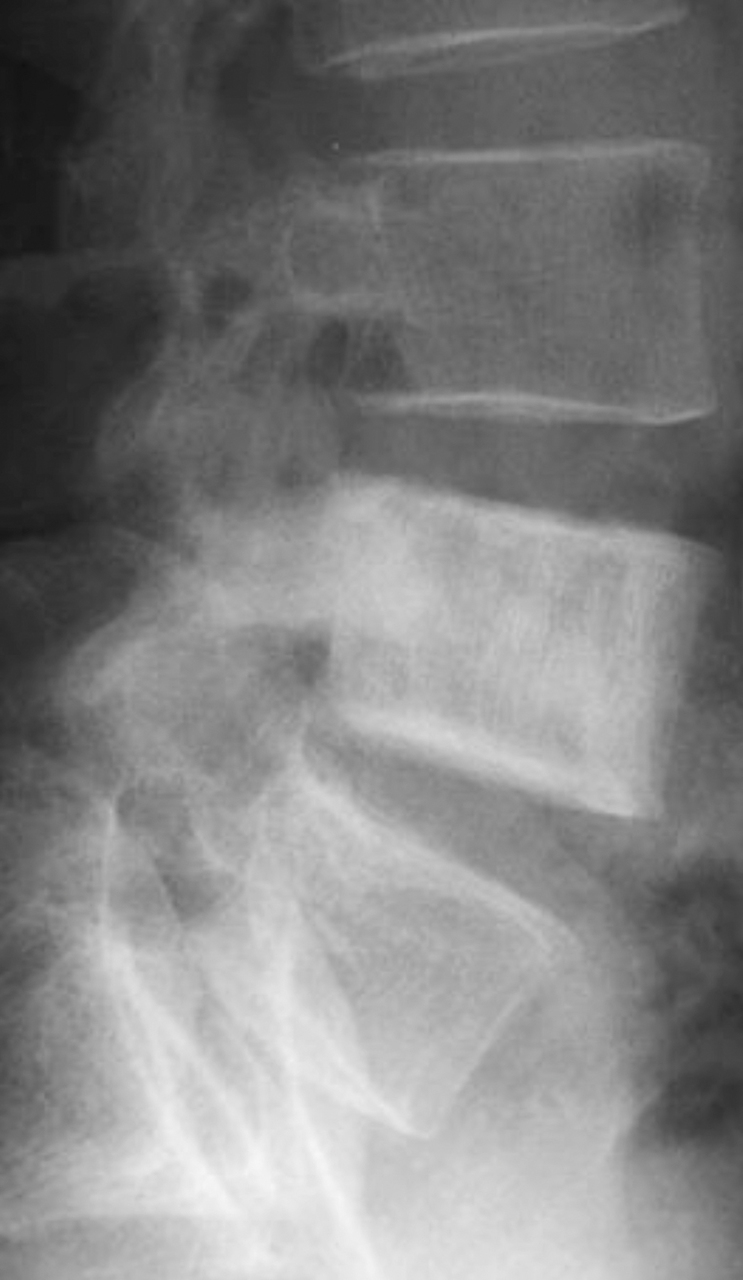

Quel est votre diagnostic ?

Il s'agit d'une vertèbre dite ivoire. Densification corporéale par une infiltration tumorale (primitive ou métastatique) ayant un fort potentiel ostéoblastique, condensant. Les métastases qui constituent la troisième famille de tumeurs osseuses sont les plus fréquentes chez l'adulte. Leur expression est souvent agressive, mais parfois très variée, parfois mixte, associant ostéolyse et condensation. Le tissu tumoral métastatique peut avoir un caractère très condensant, allant jusque dans certains cas à décrire la classique "vertèbre ivoire" avec un corps vertébral totalement densifié.